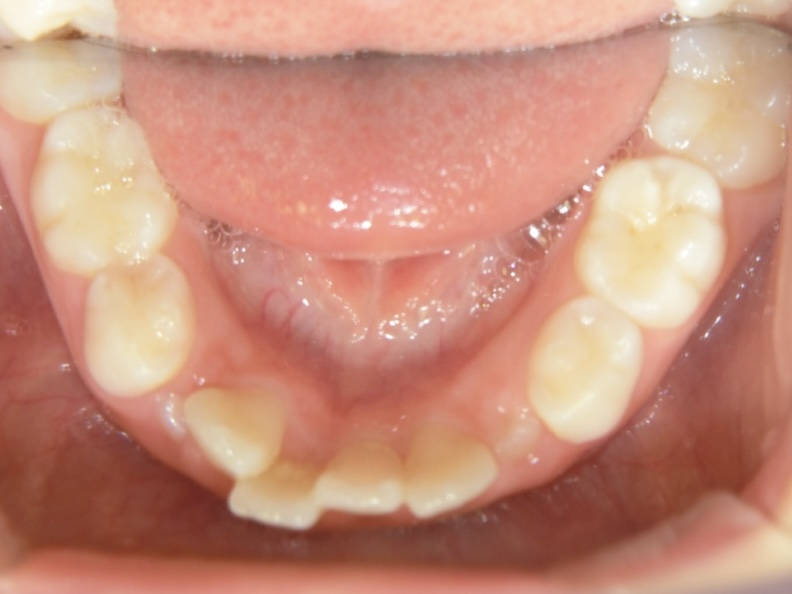

Before 2

8歳女児 ガタガタが気になる

8歳女の子の症例です。

永久歯の萌出スペースが不足しており、ガタガタの歯並びを気にされてご来院されました。

主訴 ガタガタした歯並び